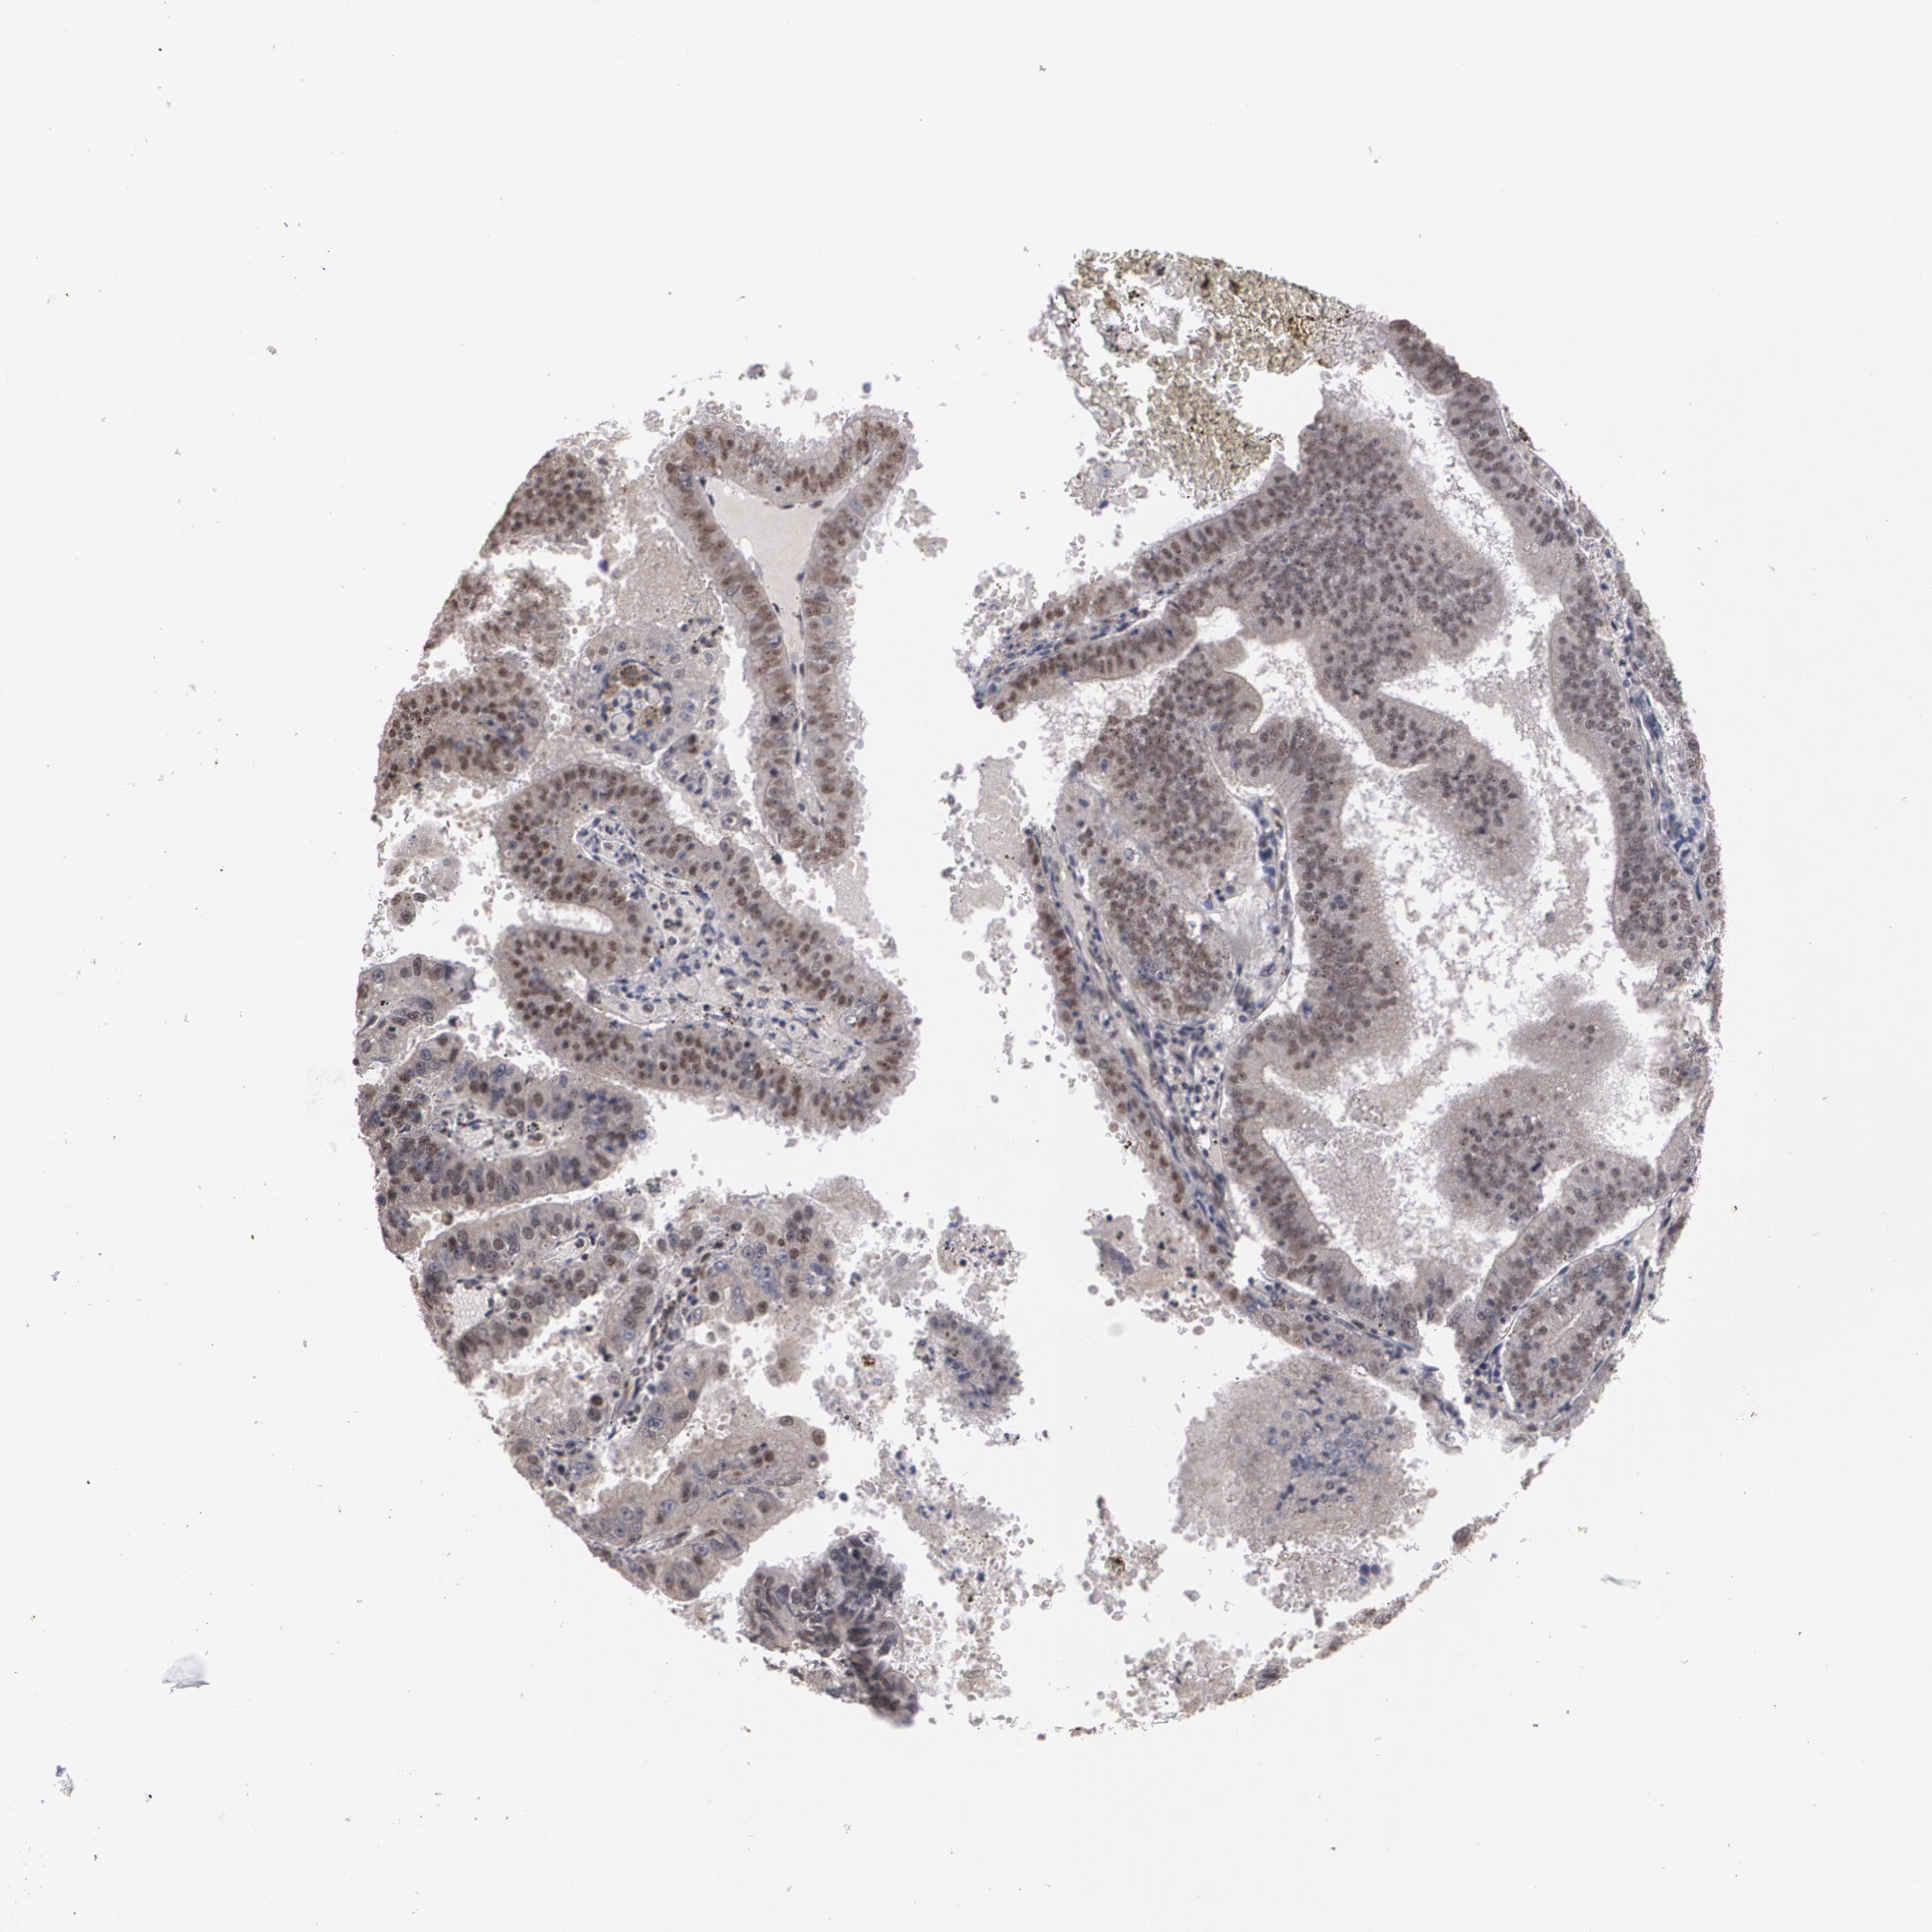

ENDOMETRIAL CANCER - Protein expressioni

A mouse-over function shows sample information and annotation data. Click on an image to view it in a full screen mode. Samples can be filtered based on level of antibody staining by selecting one or several of the following categories: high, medium, low and not detected. The assay and annotation is described here.

Note that samples used for immunohistochemistry by the Human Protein Atlas do not correspond to samples in the TCGA dataset.

Antibody stainingi

Antibody staining in the annotated cell types in the current human tissue is reported as not detected, low, medium, or high, based on conventional immunohistochemistry profiling in selected tissues. This score is based on the combination of the staining intensity and fraction of stained cells.

Each image is clickable and will lead to virtual microscopy that enables deeper exploration of all samples and also displays staining intensity scores, fraction scores and subcellular localization as well as patient and tissue information for each sample.

Antibody HPA001665

Staining

High

Medium

Low

Not detected

Intensity

Strong

Moderate

Weak

Negative

Quantity

>75%

75%-25%

<25%

None

Location

Nuclear

Cytoplasmic/membranous

Cytoplasmic/membranous,nuclear

Adenocarcinoma, NOS

Neoplasm, malignant, NOS